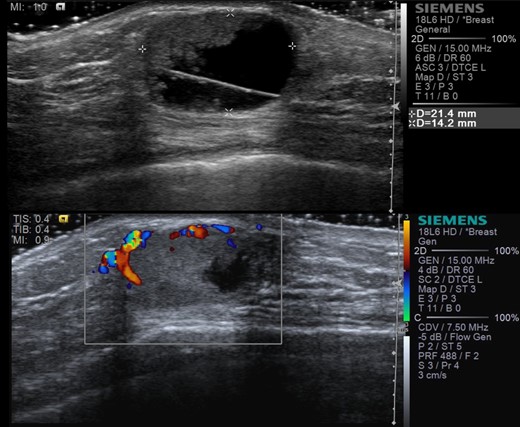

Ultrasound studies showed a well-defined solid-cystic nodule measuring approximately 2.1 cm × 2.1 cm × 1.4 cm with internal septation. There was a large, peripherally located solid component with internal vascularity seen (Fig. 2). The lesion was deemed indeterminate and an excision biopsy was performed. The histology report revealed a Grade 1 IPC with no lymphovascular invasion (Figs 3 and 4).

Ultrasound images showing right retroareolar complex cyst with indeterminate solid component (a) and internal vascularity (b).

Most of the patients (15/18 cases) in our review underwent sonographic assessment while slightly less than one-third had additional mammography performed. Typical sonographic appearance of IPC is that of a hypoechoic area with soft tissue echoes projecting from the wall of the cyst [8, 9].

However, significant variation exists on sonography ranging from intraductal lesions to predominantly solid lesions with the intraductal or intracystic mass totally filling the duct [9]. On an important note, IPCs are highly vascular tumours demonstrating a characteristic flow pattern on colour-flow studies, which are sensitive to identification of even very small IPCs. In our case, ultrasound showed a mainly cystic nodule with a peripherally located solid component within which internal vascularity was seen.